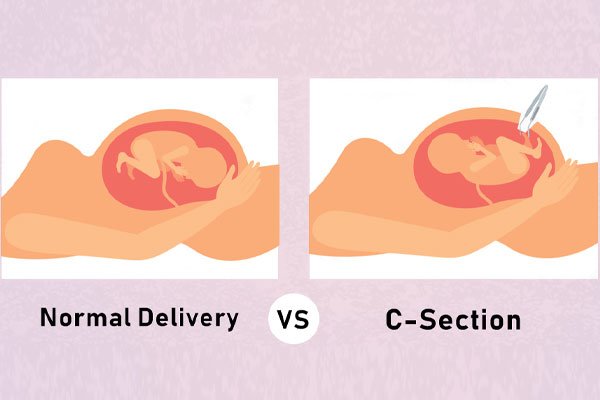

It is defined as a natural way of bringing the baby into this world. It is...